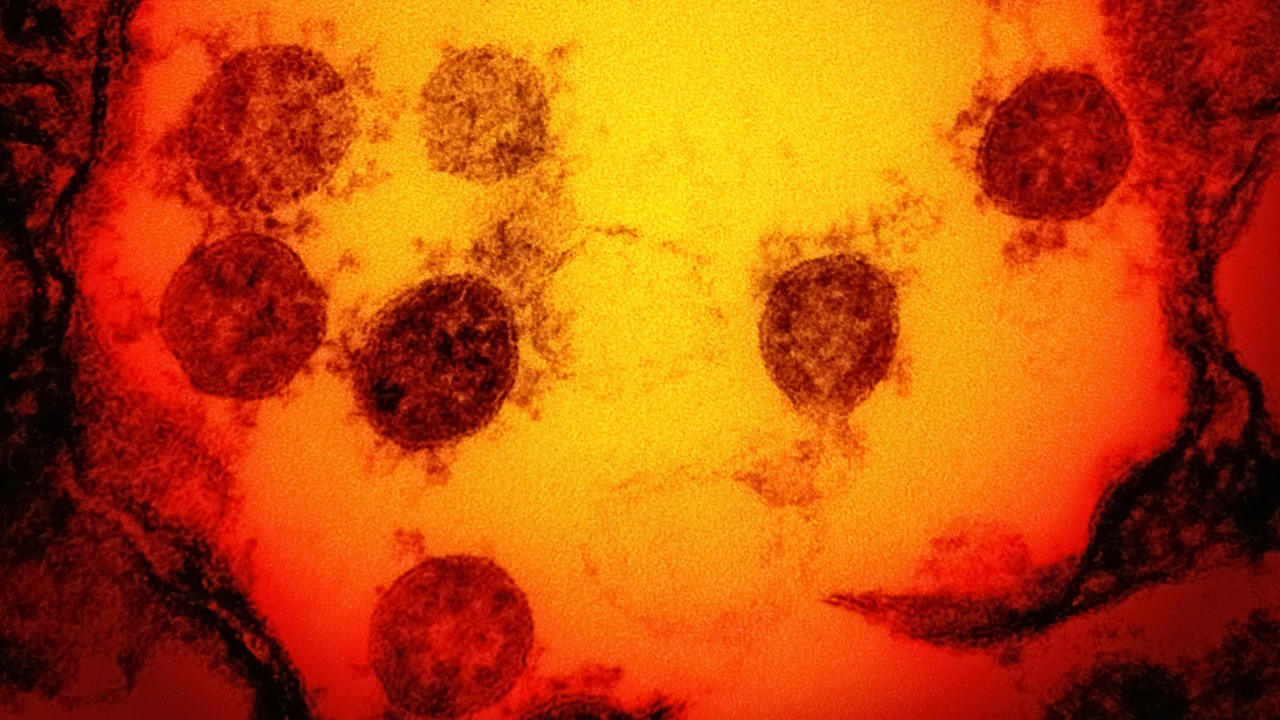

The ‘mutant’ humans who shrug off every known virus

Read More: The ‘mutant’ humans who shrug off every known virusAcross the world, only a few dozen people appear to carry a genetic glitch that lets them brush off viruses…

Ancient DNA exposes virus that hacked its way into human genes

Read More: Ancient DNA exposes virus that hacked its way into human genesAncient DNA is turning human evolution into a crime scene reconstruction, and one of the prime suspects is a herpesvirus…